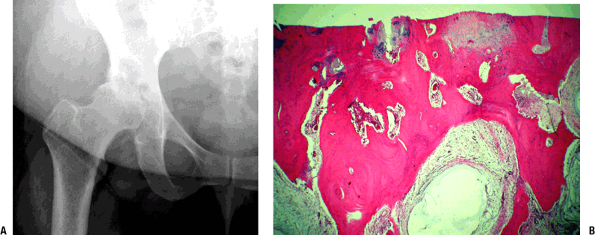

Figure 21-4

Osteoarthritic hip. (A) Radiograph showing advanced osteoarthritis with

complete loss of surface cartilage, exposing dense subchondral bone.

Numerous cysts are present filled with amorphous myxoid material. The

bone adjacent to the cysts is sclerotic, representing altered

mechanical force transmission around the area of the cyst normally

filled with cancellous bone. (B) Photomicrograph showing advanced

osteoarthritis with complete loss of surface cartilage, exposing dense

subchondral bone. There is no definable articular cartilage present.

Numerous cysts are present filled with amorphous myxoid material; the

filled with cancellous bone.

Radiologic Findings (see Fig. 21-4)

The classic findings are of joint space

narrowing (reflecting loss of cartilage), subchondral sclerosis

(increased bone formation secondary to increased force across the joint

surface), osteophyte formation (progressive remodeling), and

subchondral cyst formation (mechanism controversial, secondary to break

in subchondral bone or arising as a result of metaplasia of subchondral

marrow in the environment of increased mechanical force).